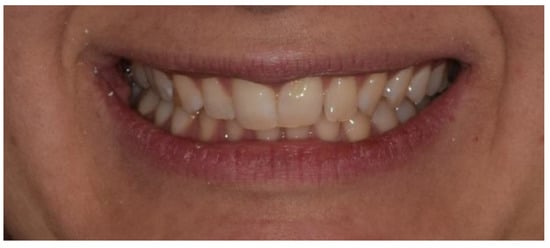

Thanks to the patient’s excellent collaboration, the optimal biomechanical control of the aligners and the patient’s growth, the treatment was successfully carried out in 18 months, reaching a dental class I, a resolution of crowding, a median diastema closure and deep bite resolution.

The leveling of the lower arch and the coordination of the arches made it possible to treat the dental class II using intermaxillary elastics (Figure 18, Figure 19 and Figure 20 and Table 4). At the end of the treatment, the patient was asked to wear removable Essix for long-term retention.

Figure 18. Post-treatment intraoral and extraoral photos of case number 2: frontal facial view (A); frontal facial view smiling (B); right facial view (C); right facial view smiling (D); right arches view (E); frontal arches view (F); left arches view (G); upper arch occlusal view (H); lower arch occlusal view (I).